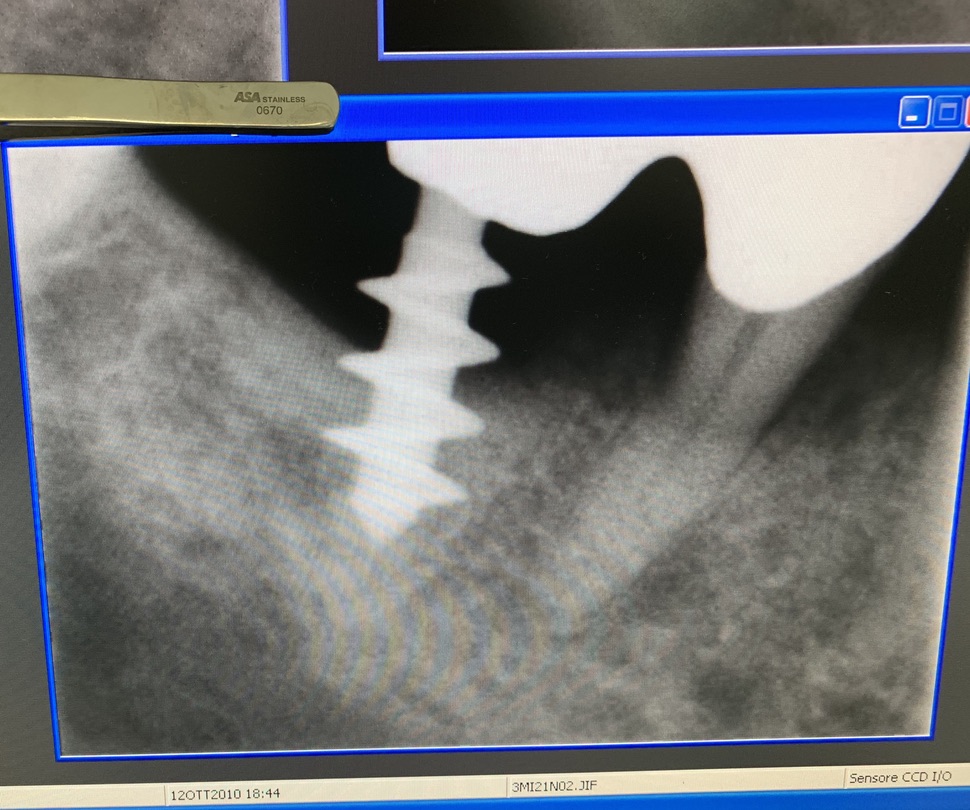

Original form of the Tramonte implant. 5 mm diameter with 3 threads. Stem diam. 2.1 mm. Neck diam. 2 mm x 5 mm in length. Grade 2 titanium. Grade 2 allowed the need to bend the implant neck to improve parallelism. It is an immediate post-extraction implant. Therefore, in the same session, extraction, boring, tapping and implant insertion. Immediately followed by monconization and the preparation of temporary crowns in light occlusion. The radiographs provided show the situation since 2010. The emergence of the thin neck favors the formation of a dense gingiva sleeve that protects against peri implantitis. The wide threads radiate the occlusal load away from the implant body, favoring the formation of a more homogeneous bone.